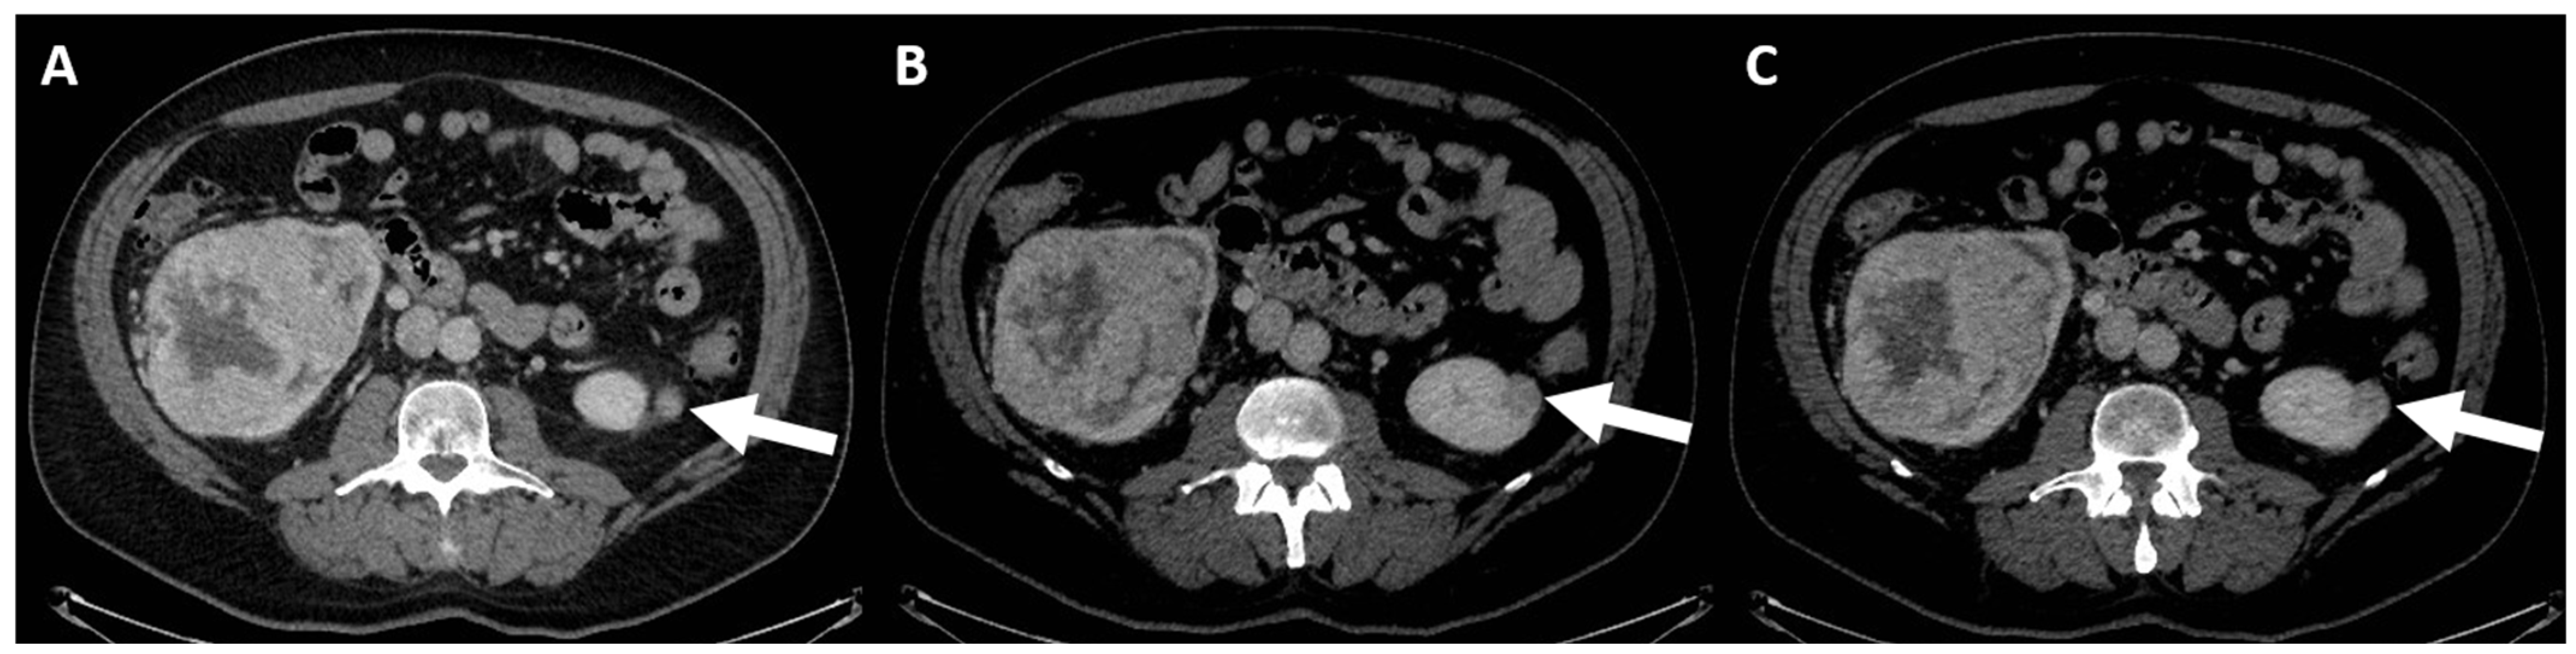

4. Computed Tomography Assessment

4.1. Lesion Density

4.2. Macroscopic Fat

4.3. Enhancement

- (e) Class IV: clearly malignant cystic mass, which includes masses characterized by the presence of one or more enhancing nodules (≥4 mm convex protrusion with obtuse margins, or a convex protrusion of any size that has acute margins). A Bosniak IV mass (Figure 5) has a malignancy rate of about 90% and therefore requires urologic consultation to perform partial or total nephrectomy [100].